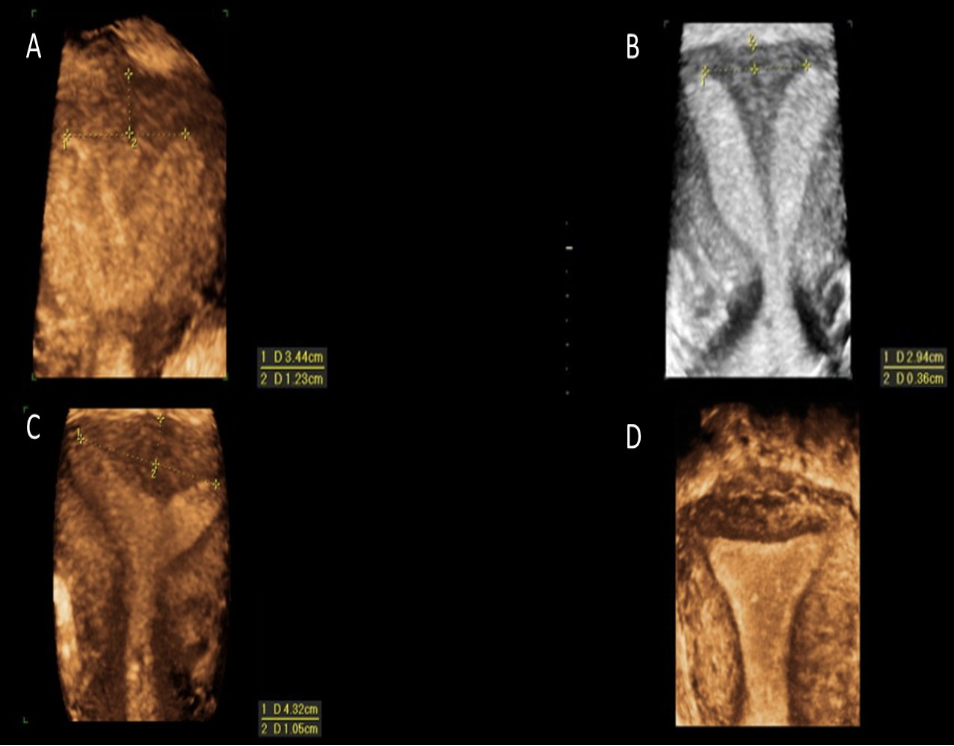

which shows arcuate uterus

a) A

b) B

c) C

d) D

which is a subseptate uterus

which congenital abn is this

a) uterine subseptus

b) uterine bicornis bicollis

c) uterine arcuatus

d) uterine bicornis unicollis